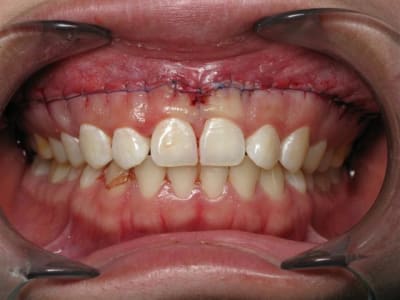

Sourire gingivale a mort, une CCM faite l'année derniere.

Morphotype epais et une bonne bande de gencive keratinisé.

Tout ce dont j'avais besoin pour changer un peu de la "routine" des resections apicales.

Mais apres analyse des photos jme suis dit que j'aurais du moins m'emballer sur la longueur !

Mais je pense que tu aurais pu aller un peu plus loin distalement. Aussi, les sutures semblent grosses et la soie n'est pas le meilleur matériel, trop de bactéries.

C'est vrai que les sutures sont degueulasses le jour de la dépose mais le titulaire est une barre de fer :)

Incision propre et franche, décollement du lambeau respectueux et atraumatique et enfin sutures fines et appropriées sont autant de facteurs importants pour avoir un joli résultat.

Quant au prix du Prolene tu peux dire à ton titulaire qu'il ne va pas se ruiner. Dommage de faire ce genre de chirurgie paro dont le but est ethétique avec un fil de suture de cette qualité ;-((